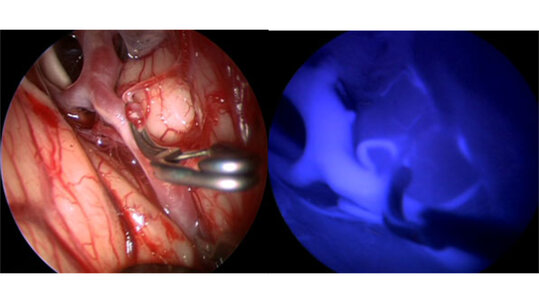

Zur Behandlung eines Aneurysma stehen zwei unterschiedliche Methoden zur Verfügung. Zum einen der interventionelle Verschluss mittels Metallspiralen (engl. Coils – deshalb auch als Coiling bezeichnet), die über einen von der Leiste vorgeschobenen Katheter in das Aneurysma eingebracht werden. Diese Therapieoption wird von einem Neuroradiologen durchgeführt. Zum anderen der Verschluss mit einem Clip (Clipping), der während einer neurochirurgischen Operation auf den Hals des Aneurysma gesetzt wird. Heutzutage ist hierzu in den meisten Fällen nur eine kleine Schädeleröffnung (Minikraniotomie) erforderlich, um den Clip sicher zu platzieren. Wichtig ist die Überprüfung der Hirndurchblutung, die durch den Clip nicht beeinträchtigt sein sollte. Neben der Erfahrung unserer vaskulären Neurochirurgen stehen zur Sicherung eines optimalen Behandlungserfolges auch modernste Techniken zur Verfügung. Zu unserem Behandlungsstandard gehören mikrochirurgische Verfahren, die von neusten endoskopischen Techniken unterstützt werden. Die intraoperative Darstellung der Hirngefäße mit Fluoreszenzfarbstoffen (ICG-Videoangiographie und ICG-Endoskopie) garantiert zusammen mit intraoperativen Ultraschalluntersuchungen und funktionellem Neuromonitoring ein bestmögliches postoperatives Resultat.

nach dem Clippen (links) und endoskopische Fluoreszenzangiographie nach dem Clippen (rechts)